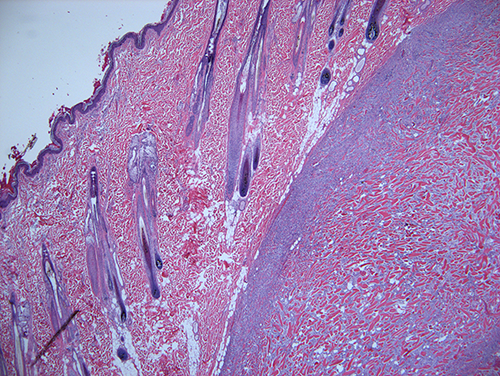

Three slides containing the excised mass were examined (Figures 3 and 4). Expanding the subcutis and elevating the dermis and epidermis was a densely cellular, well demarcated, expansile, unencapsulated nodular neoplasm. Neoplastic cells were arranged in bundles and streams supported by a dense fibrovascular to collagenous stroma; importantly, there were many haphazardly arranged thick eosinophilic homogenous hyalinized collagen fibers. Neoplastic spindle cells had indistinct cell borders, moderate amounts of lightly eosinophilic cytoplasm, a single ovoid nucleus and finely stippled chromatin with occasional nucleoli. There was mild pleomorphism of the cells, and a low mitotic count (2 observed per 2.37mm2). There was minimal inflammation and no evidence of necrosis. The surgical margins were wide, with normal fat completely surrounding the mass.

Figure 3: Histologic section of a subcutaneous keloidal fibroma from a 3-year-old male castrated dog. A well demarcated, unencapsulated spindle cell neoplasm elevates the dermis and epidermis. H&E 20x magnification.

Figure 4: Histologic section of a subcutaneous keloidal fibroma from a 3-year-old male castrated dog. Neoplastic fibroblasts surround numerous large fibrils and bundles of hyalinized eosinophilic collagen. H&E 200x magnification